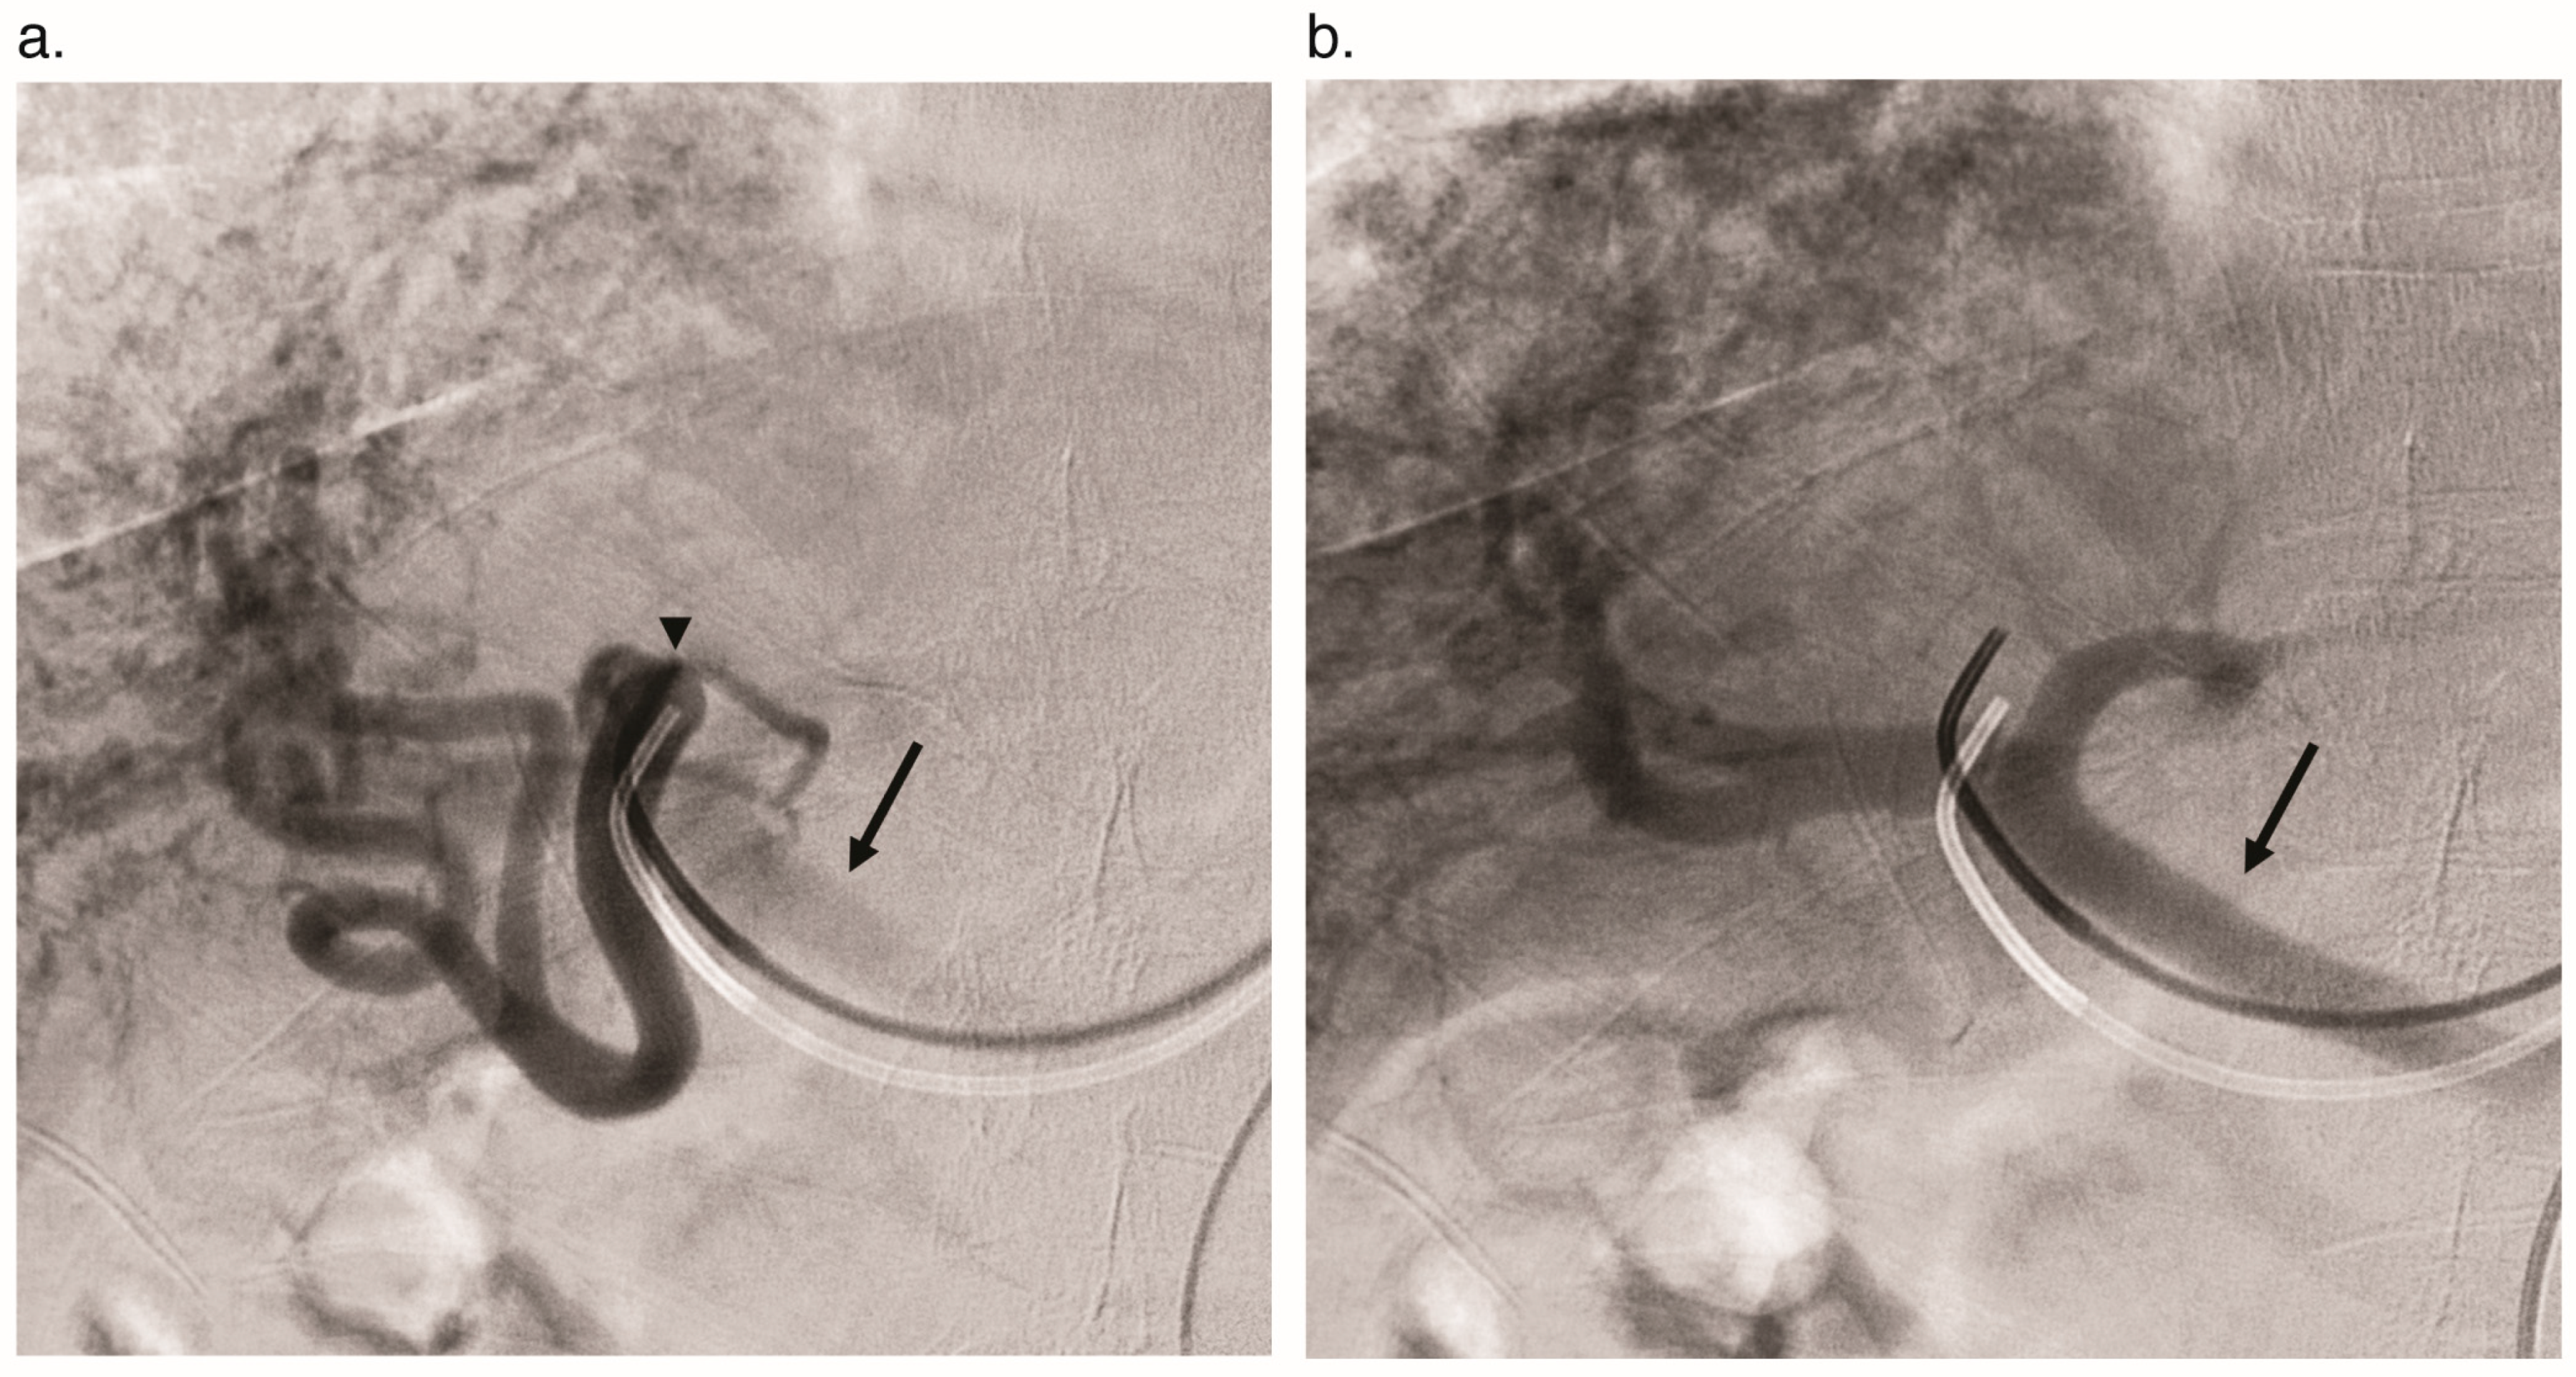

4.3. Catheter Angiography

- Chavan, A.; Luthe, L.; Gebel, M.; Barg-Hock, H.; Seifert, H.; Raab, R.; Kirchhoff, T.; Schmuck, B. Complications and clinical outcome of hepatic artery embolisation in patients with hereditary haemorrhagic telangiectasia. Eur. Radiol. 2013, 23, 951–957. [Google Scholar] [CrossRef] [PubMed]